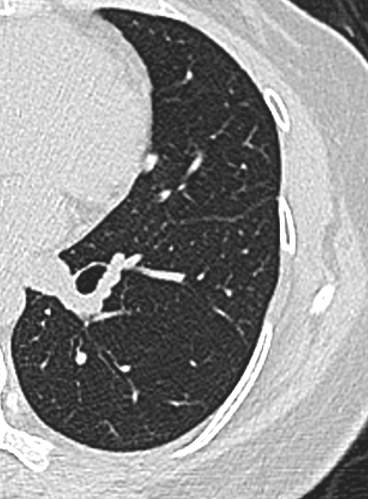

中年女性,既往体健。

21年底左下肺,直径5.2mm:

23年初复查CT左下肺GGO有所增大,直径:6.9mm

问题来了,一年多后复查GGO有增大,考虑恶性吗,需要手术吗,病理考虑什么?